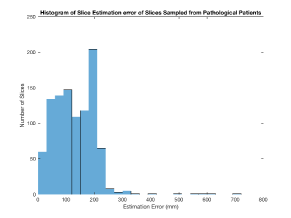

We use Siddon-Jacobs ray tracing [15] to generate Digitally Reconstructed Radiographs (DRRs) from the above described data. For training, we equally sample DRRs on equidistant half-spheres around 51 CT volumes at distances of 80cm, 60cm, and 40cm, between and around all three co-ordinate axes. For validation, we generate 1000 DRRs with random rotation parameters within the bounds of the training data at 60cm distance from the volumetric iso-centre. We trained on healthy volunteer data and tested on nine healthy and ten randomly selected pathological volumes (eight lung cancer and two spinal pathologies). Our approach is able to predict DRR transformations relative to the trained reference co-ordinate system with an average translation error of 106mm and plane rotation for healthy patients, and 130mm and average error for pathological patients. An example is shown in Fig. 4e,f. Note that these values are good enough to robustly initialize intensity-based registration refinement. SVRNet prediction can be improved by generating a denser training data set, in particular, in more equidistant half-spheres.